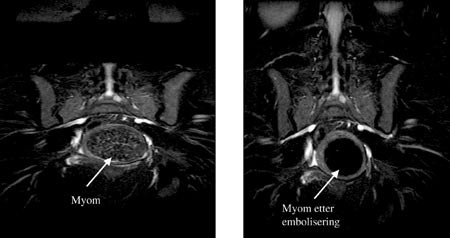

Arteria femoralis communis punkteres perkutant i høyre lyske og a. iliaca interna kateteriseres med 4 F-kateter med fleksibel tupp. Deretter tilstrebes selektiv kateterisering av a. uterina slik at den cervikovaginale gren av arterien bevares ved emboliseringen. Røntgenkontrast blandet med polyvinylalkoholpartikler av 355 – 500 m størrelse injiseres langsomt. Injiseringen avsluttes når det ikke lenger påvises sirkulasjon til myomet eller myomene. Samme prosedyre gjentas på motsatt side via samme tilgang i lysken. Dermed unngås nytt innstikk. Det er viktig å påvise eventuell kollateral sirkulasjon fra a. uterina til det ene eller begge adnekser fordi det kan redusere emboliseringseffekten. I slike tilfeller kan det være aktuelt først å embolisere kollateralene. Ved kateteriseringen kan det oppstå arteriespasme i området der katerspissen befinner seg. Dette kan behandles med lokal injeksjon av nitroglyserin. Avslutningsvis utføres aortagrafi for å utelukke eventuell sirkulasjon til myom fra a. ovarica. Figur 1 viser selektiv angiografi av venstre a. uterina med oppladning i stort myom før og etter embolisering. Figur 2 viser stort intramuralt myom før og ni måneder etter embolisering.